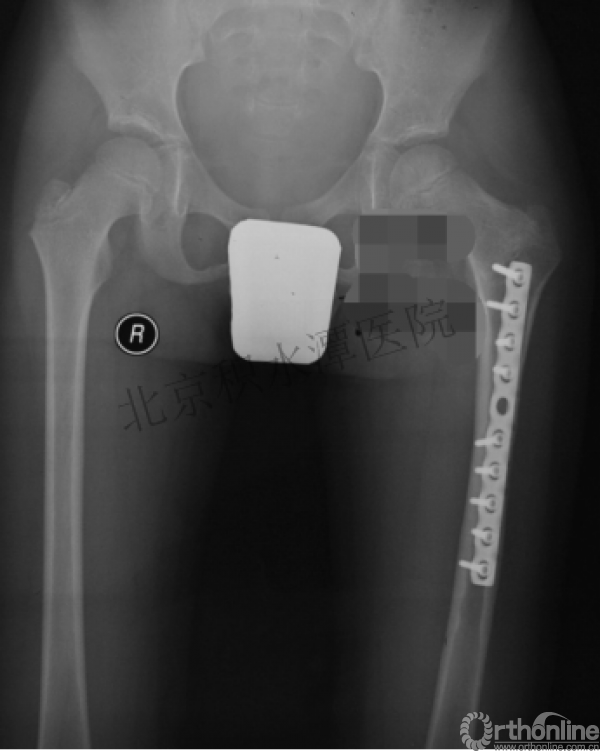

病例分享二

2岁、股骨干骨折,切开+内固定

简单牵引即可!为什么要如此大动干戈?

现实中又是怎样的呢?不知道这属于知识缺乏范畴还是道德品质问题?

匪夷所思!